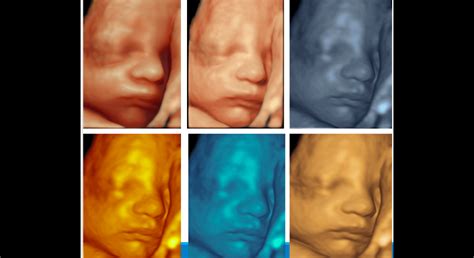

Približne v polovici tehotenstva, okolo 20. týždňa, maternica siaha k úrovni pupka. V tomto období nastávajúce matky po prvýkrát pocítia pohyby svojho dieťatka, čo robí tehotenstvo reálnejším a intímnejším. Plod je dlhý 18 až 23 cm a váži takmer 500 g, čím dosahuje polovicu svojej pôrodnej dĺžky. Svaly sa posilňujú, nervová sústava dozrieva a kostra sa spevňuje. Pohyby sú koordinovanejšie a dostatočne silné na to, aby ich matka cítila. Uši sú dostatočne vyvinuté na rozpoznávanie zvukov. Dieťa má pravidelné intervaly bdenia a spánku a dokáže robiť grimasy. Na hlave sa objavujú vlasy a obočie. Koža je ružová, vráskavá a pokrytá belavou hmotou - vernixom, ktorý chráni pokožku. U chlapcov začínajú zostupovať semenníky.

Maternica rastie a dosahuje veľkosť basketbalovej lopty. Dieťa je dlhšie ako 30 cm a váži takmer 1000 g. Pohyby sú koordinované, dieťa "bicykluje" nožičkami a naráža nimi do steny maternice, čím si precvičuje chôdzu. Vytvára si pevný stisk. Dieťa môže otvárať a zatvárať oči a reaguje na svetlo. Hlasivky sú funkčné, aj keď prvý zvuk vydá až pri pôrode. Objavuje sa štikútavka, ktorá otriasa celou maternicou. Dieťa narodené v tomto období má pri intenzívnej starostlivosti šancu prežiť.